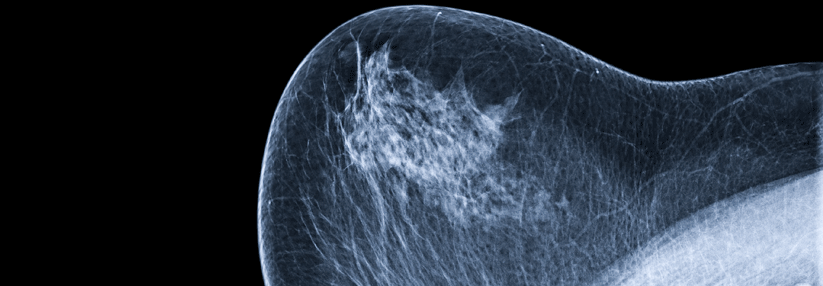

Frauen mit fortgeschrittenem HR+/HER2- Brustkrebs profitieren von der Behandlung mit CDK4/6-Inhibitoren. Das bestätigte sich nun in zwei Langzeitanalysen. (Agenturfoto) Frauen mit fortgeschrittenem HR+/HER2- Brustkrebs profitieren von der Behandlung mit CDK4/6-Inhibitoren. Das bestätigte sich nun in zwei Langzeitanalysen. (Agenturfoto) © LIGHTFIELD STUDIOS – stock.adobe.com